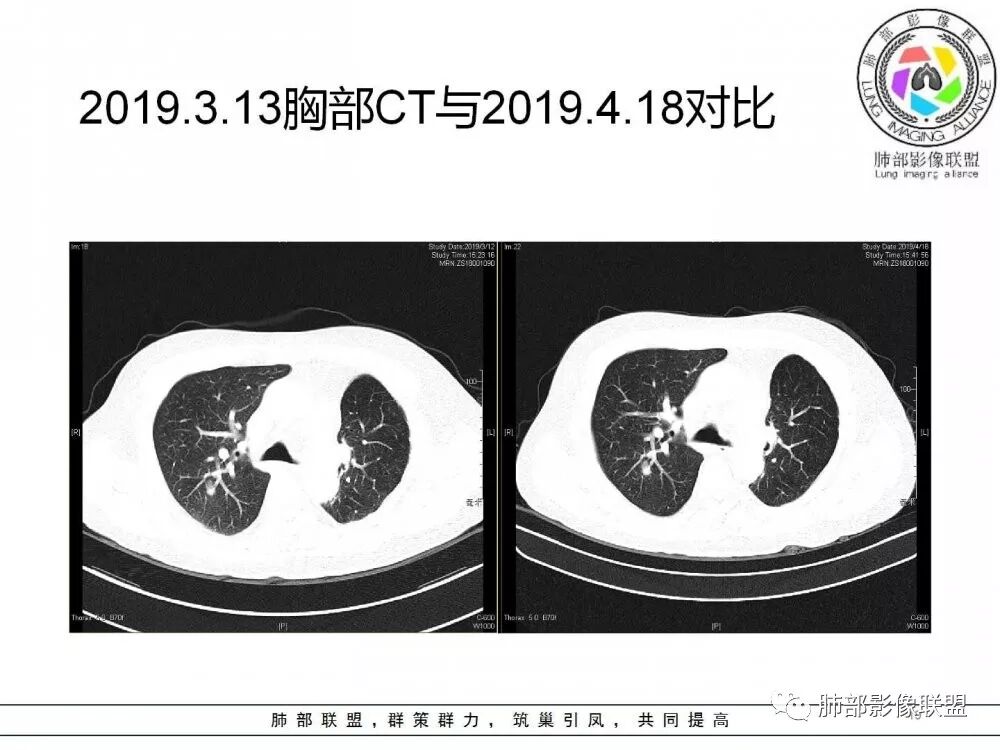

肺部病灶从2月份就开始有了,应该最早说是1月7号就有了,到3月13号稍微增大一点,到后面几乎就没变化了,到5月份好像稍微大一些,炎性肯定是炎性,就是这个炎性是到底什么病变呢?其实本没变化,它特点一个是在叶裂上,跟血管关系密切,但是病灶边缘稍收缩,病灶这么没有太大变化,我还是支持炎性病变。

因为这个长轴似乎跟支气管走行一致的,其实治疗效果不是很理想,我先把性质定为炎性。因为这个病灶它沿着血管支气管走行的方向,大家都考虑隐球菌,这么久病灶无明显变化,它跟血管束关系很密切。我犹豫就在此,到底是IgG4还是隐球,大方向是炎性,不符合的就是也在激素治疗。